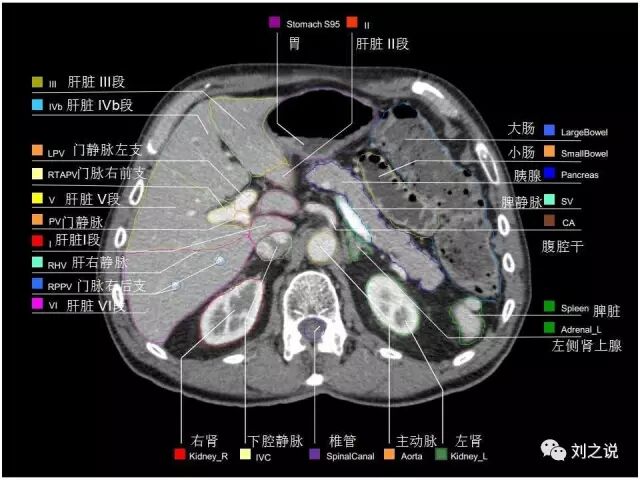

【解剖】高清实用 腹部CT断层

参考RTOG共识和3D-body解剖。

来源:刘之说